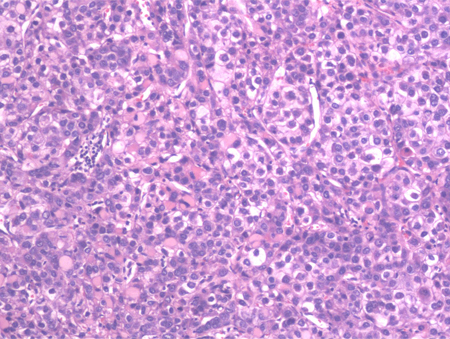

liver biopsy

Test

Most of the time, the diagnosis of HCC can be made radiologically in patients with cirrhosis without the need for liver biopsy. However, biopsy should be considered if the lesion remains indeterminate and in order to establish diagnosis of HCC in patients without cirrhosis or chronic hepatitis B virus infection.[7]

An ultrasound-guided percutaneous liver biopsy is favoured.

Core needle biopsy may be considered in certain clinical scenarios.[2]

Biopsy of liver lesions may also be necessary if clinical features suggest the possibility of metastatic liver disease or cholangiocarcinoma.

[Figure caption and citation for the preceding image starts]: High-power view of haematoxylin and eosin stained section of a well-differentiated HCC. Predominantly a solid pattern of growth with some nesting of malignant cells, separated by compressed sinusoids; some cells have clearing of the cytoplasmFrom the personal collection of Badar Muneer MD, Florida Hospital Transplant Center, Orlando, FL; used with permission [Citation ends].